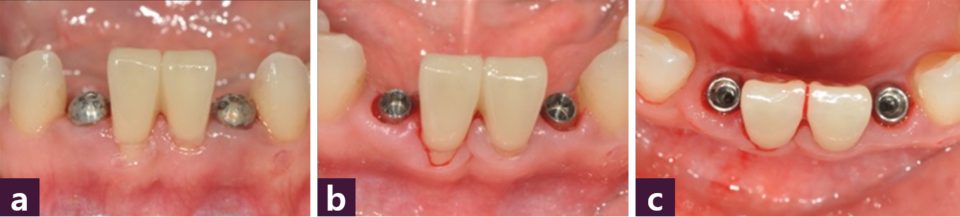

최소침습적 방법으로 Magi Core를 식립한 후 치근 방향을 교정하였다 [그림 9].

이후 healing cap을 체결하여 sub-gingival level이었던 margin 을 정리하였다 [그림 10]

마지막으로 Short Abutment를 사용하여 zirconia cement retained type 최종 보철물을 완성하였다 [그림 11, 12].